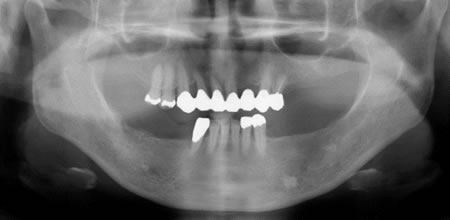

■治療前